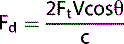

THE DOPPLER EQUATION

The Doppler equation shows the mathematical relationship between the detected Doppler shifted signal (Fd) and the blood flow velocity (V):

1 image

where:

Fd = Doppler shifted signal

Ft = transmitted Doppler frequency

c = the propagation speed of ultrasound in soft tissue (1540 ms−1)

V = velocity of the moving blood

θ = the angle between the Doppler ultrasound beam and the direction of blood flow

The number 2 is a constant indicating that the Doppler beam must travel to the moving target and then back to the transducer.

Equation 1: The Doppler equation.